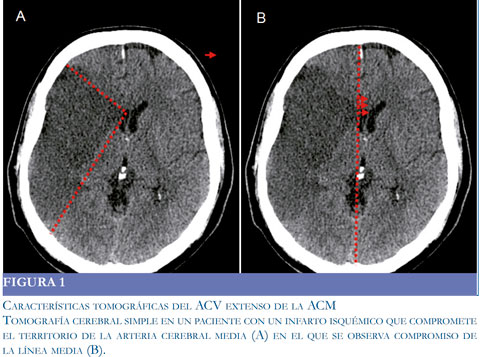

En todos los pacientes se realizó tomografía simple en la primera hora luego del ingreso a la clínica. Los signos tempranos vistos con mayor frecuencia correspondieron a hiperdensidad de la arteria cerebral media (Signo de la cuerda) y asimetría de la cisura de Silvio. Otros hallazgos correspondieron a hipodensidad en el área de la cerebral media, sin compromiso de la línea media ni de la morfología del sistema ventricular. Los pacientes que fueron trom-bolisados con rt-PA tuvieron TAC cerebrales simples normales tomadas en las 3 primeras horas del evento. Todas las tomografías de control tomadas entre las 24 y 48 horas del ingreso o post-HD, mostraron aparición del área de infarto (los que tenían TAC previamente normal), aumento del área de isquemia, signos de edema cerebral, obliteración del sistema ventricular y en dos casos signos de transformación hemorrágica espontánea (Figura 1).

El estudio imaginológico permite facilitar la toma de decisiones frente a la HD, especialmente en fases tempanas (1, 8, 10) y deben realizarse al ingreso del paciente e inmediatamente si hay deterioro clínico (1). Entre los hallazgos imaginológicos asociados al ACV maligno y que se utilizan para indicar la HD,se observa compromiso mayor del 50% del territorio de la ACM, compromiso isquémico en dos o más territorios, evidencia de edema en el TAC inicial ydesviación de la línea media mayor a 5 mm.Una alternativa para el diagnóstico temprano de ACV maligno, es la utilización de técnicas de difusión por cualquier método (TAC o RM), las cuales muestran compromiso de un volumen mayor a 145 cc en el territorio de la ACM (1-3, 5), sin embargo utilizando esta misma técnica se ha demostrado que con tan solo un volumen comprometido superior a 82 cc se puede establecer un mal pronóstico evolutivo del ACV (1, 8). Últimamente se han incluido nuevos criterios con métodos de perfusión cerebral que hablan de un compromiso mayor del 28% del territorio de la ACM como factor pronóstico de mortalidad (9). Adicionalmente tienen utilidad en la decisión de si un paciente es candidato para trombolisis sistémica o combinada. En esta serie un número importante de pacientes de ambos grupos fueron trombolizados por vía sistémica, decisión que puede ser controvertida. Sin embargo estos pacientes tuvieron TAC cerebrale simple normales y cumplieron con los criterios de indicación de procedimiento. Sin embargo si se hubieran utilizado técnicas de perfusión o difusión, la decisión podría haber sido no realizarla o en algún caso utilizar trombolisis combinada.